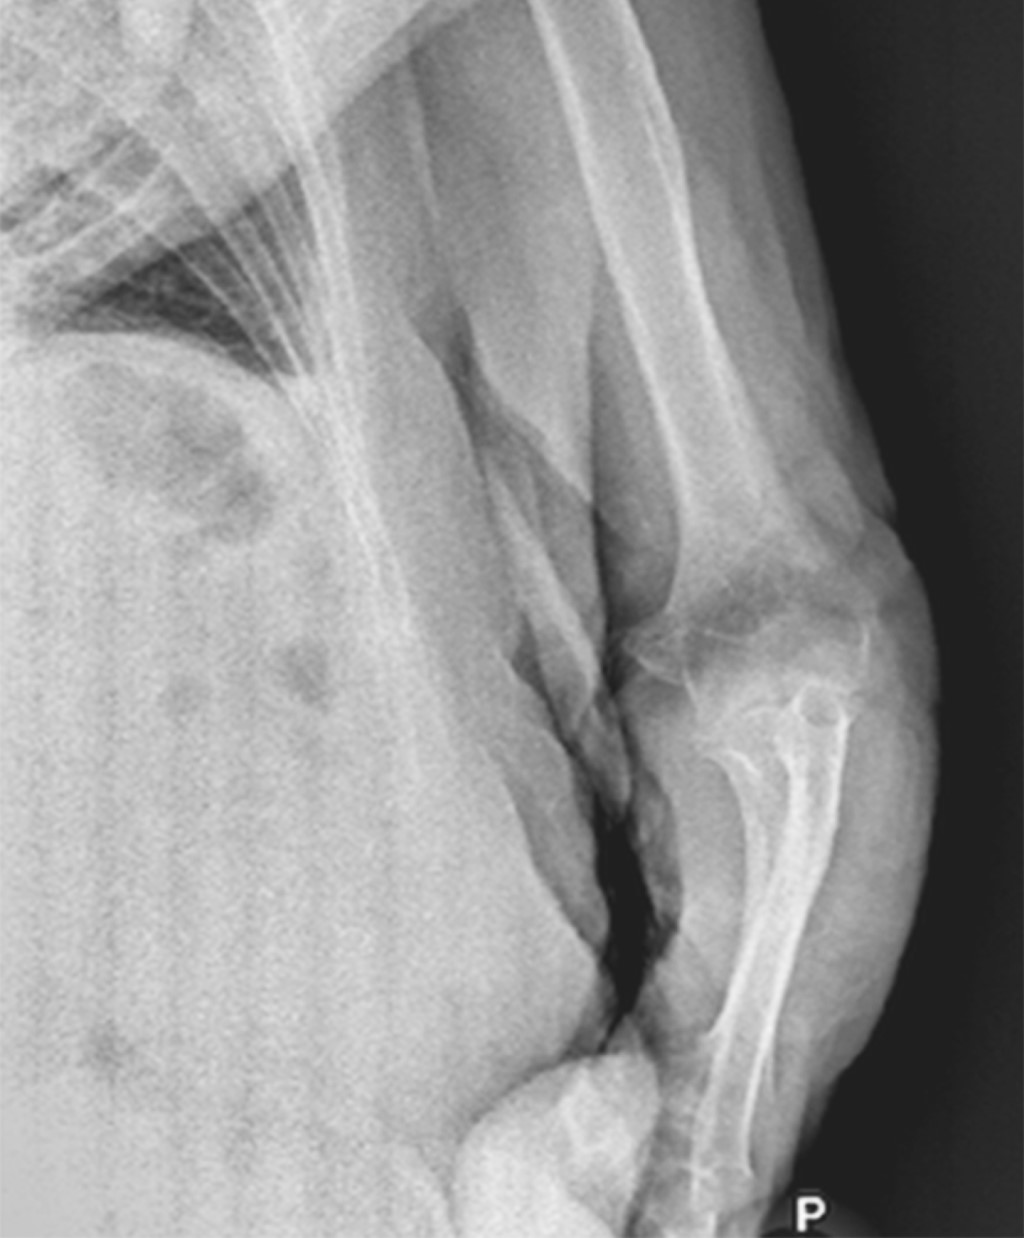

Paciente femenino de 86 años es traída al servicio de urgencias tras caída desde su propio plano de sustentación. El motivo de consulta era dolor en hombro izquierdo y codo ipsilateral. En la exploración física se observaba deformidad en codo y a paciente con miembro torácico por encima de la cabeza, siendo sostenido por extremidad contralateral para disminuir el dolor. La extremidad torácica izquierda se encontraba en abducción máxima y la paciente no era capaz de aducir el hombro. La cabeza humeral era palpable en el borde inferior de la axila. A la exploración neurovascular no se encontraron datos que sugirieran lesión. Radiografías de codo y hombro en proyección anteroposterior y lateral mostraron luxación inferior del hombro (Figuras 1 y 2), así como luxación posterior del codo sin lesión ósea asociada. Ambas lesiones fueron manejadas en quirófano mediante reducción cerrada con paciente bajo sedación. La luxación inferior del hombro fue reducida mediante tracción-contra-tracción del húmero con posterior aducción del hombro. La articulación del codo fue reducida mediante tracción axial con la muñeca en supinación con posterior flexión. Se realizó exploración neurovascular al término donde no se observaron lesiones. Se obtuvieron radiografías de control que evidenciaron correcta localización de la articulación del codo (Figuras 3 y 4) así como de la cabeza humeral (Figura 5). Debido a la mejoría, la paciente fue egresada con férula a 90o e inmovilizador de hombro, iniciando rehabilitación a las 2.5 semanas con movimientos pasivos pendulares de hombro y movimientos de flexión y extensión de codo. El seguimiento se da en la consulta externa a las cuatro semanas, tres y seis meses evolucionando de manera favorable con reincorporación completa a sus actividades de la vida diaria.

Figura 1

Figura 2